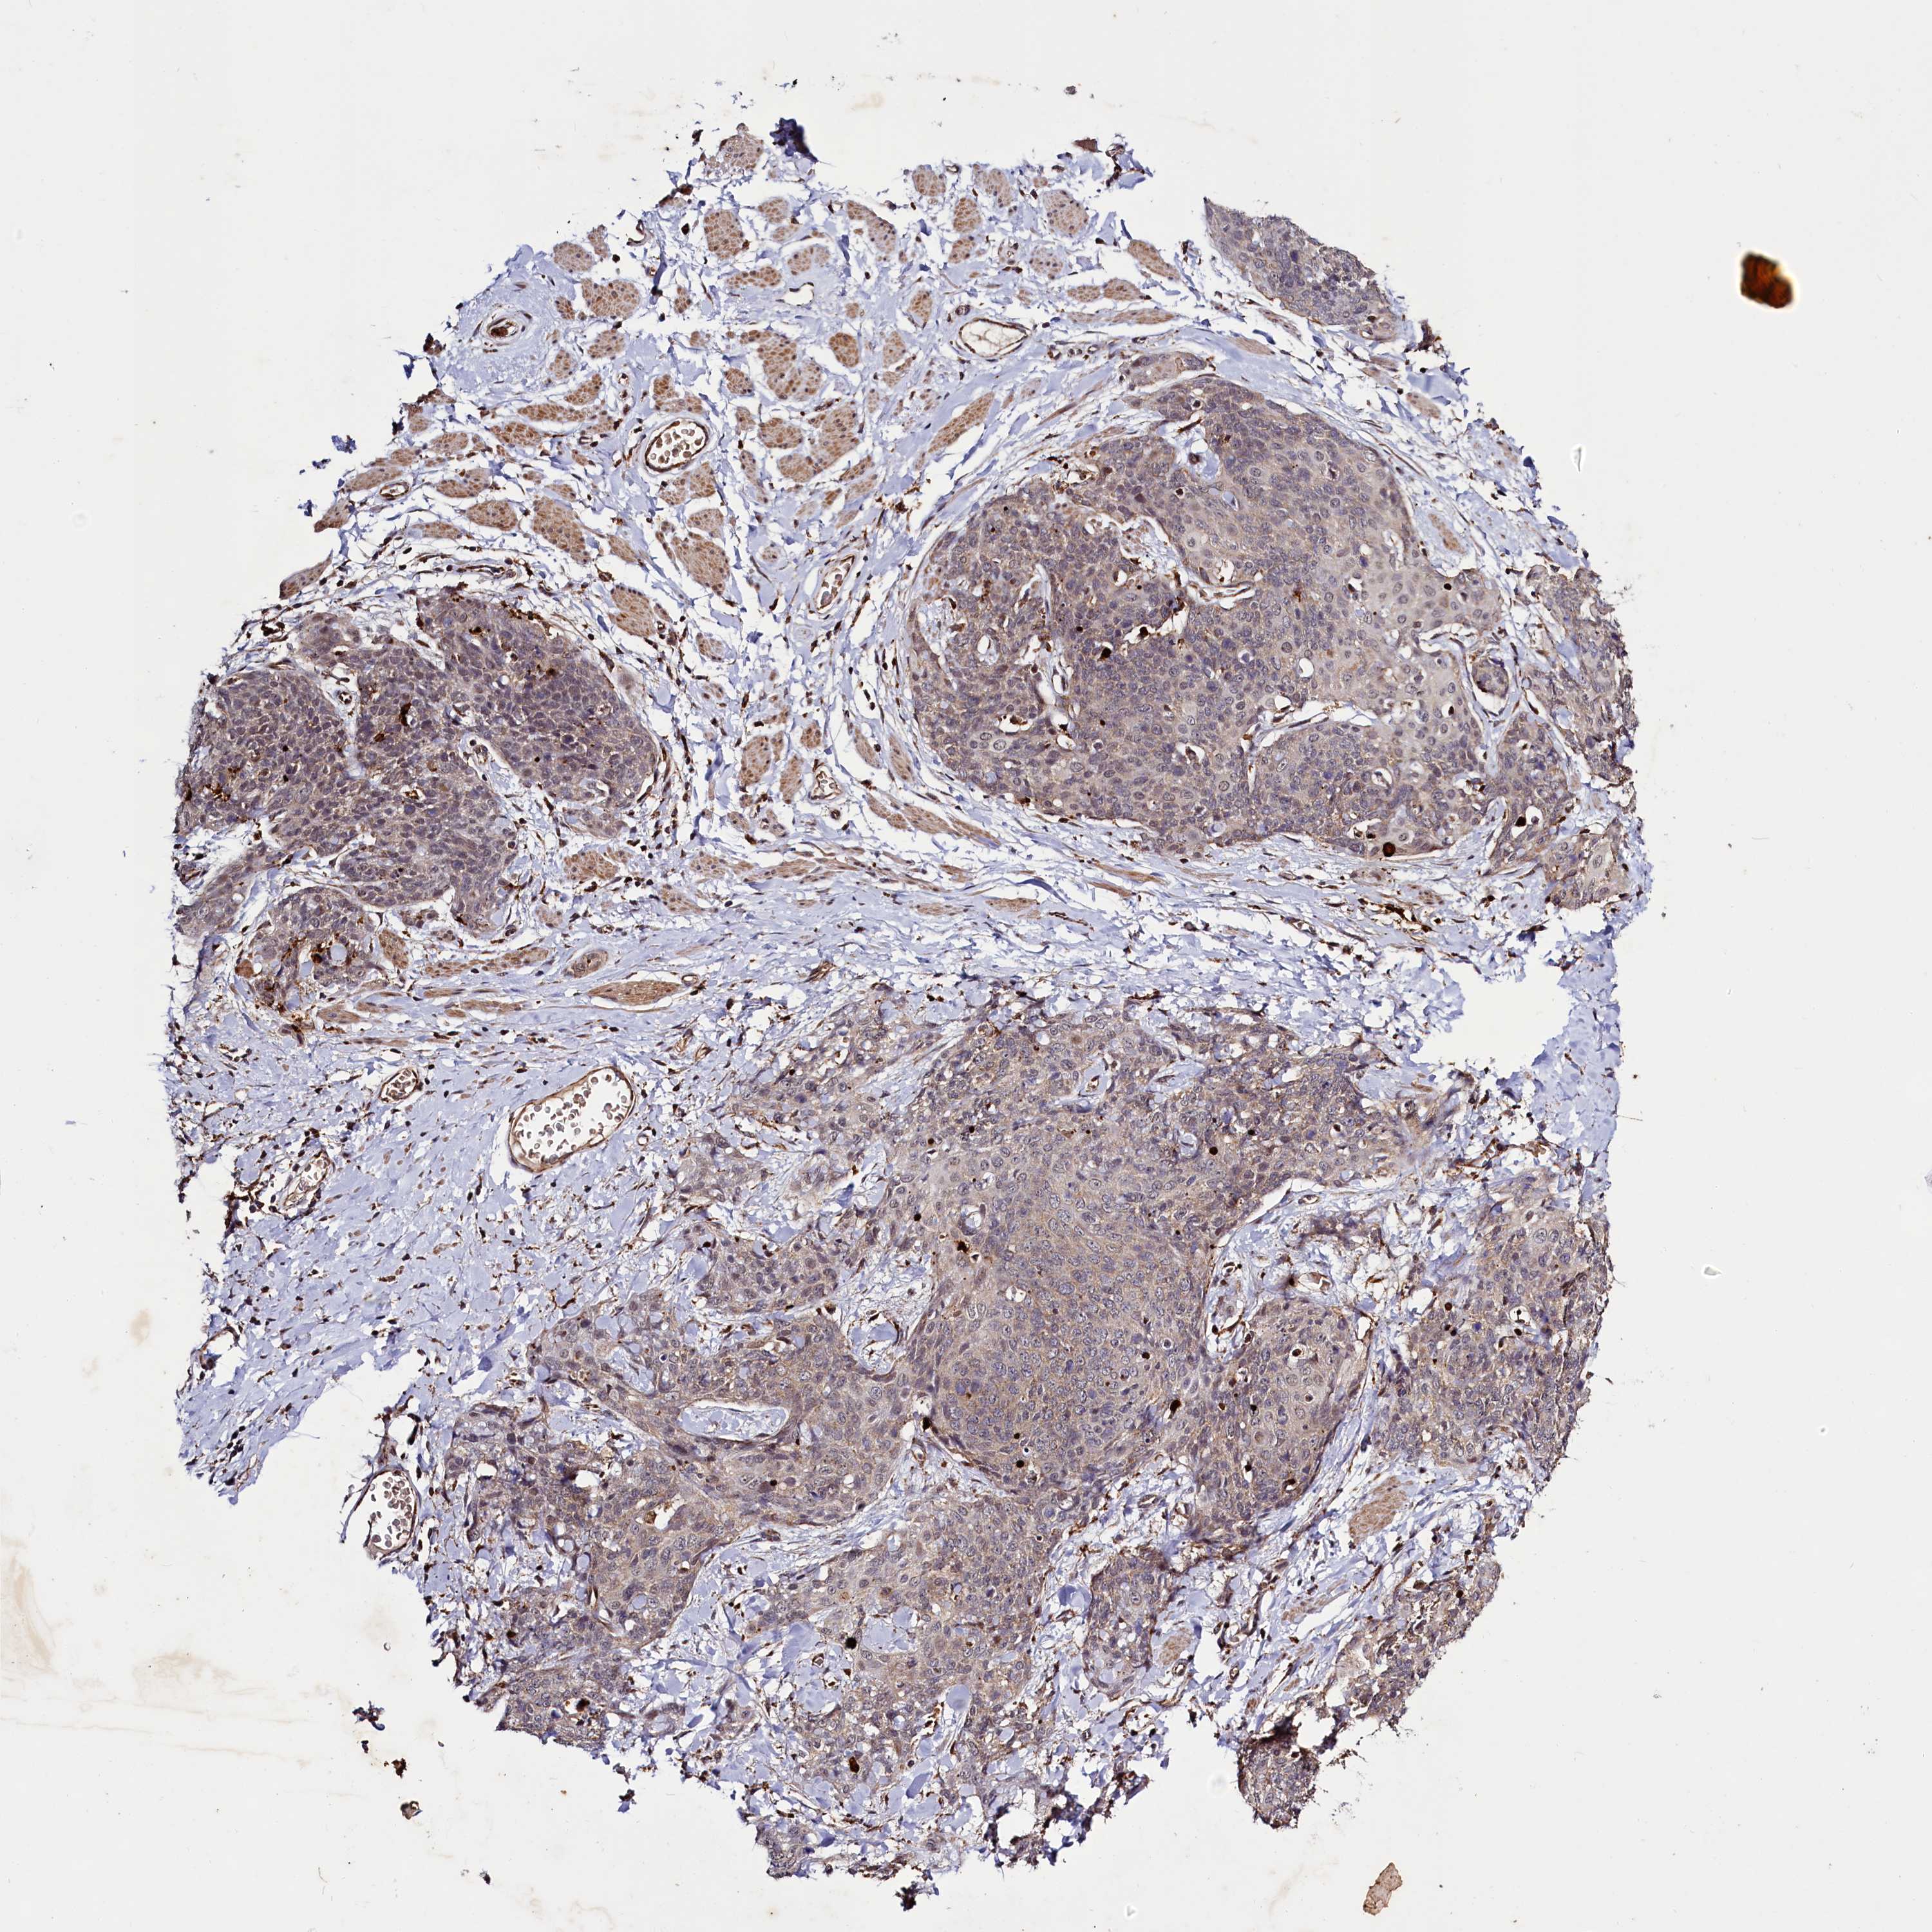

SKIN CANCER - Protein expressioni

A mouse-over function shows sample information and annotation data. Click on an image to view it in a full screen mode. Samples can be filtered based on level of antibody staining by selecting one or several of the following categories: high, medium, low and not detected. The assay and annotation is described here.

Antibody staining in the annotated cell types in the current human tissue is reported as not detected, low, medium, or high, based on conventional immunohistochemistry profiling in selected tissues. This score is based on the combination of the staining intensity and fraction of stained cells.

Each image is clickable and will lead to virtual microscopy that enables deeper exploration of all samples and also displays staining intensity scores, fraction scores and subcellular localization as well as patient and tissue information for each sample.

Antibody HPA039016

Squamous cell carcinoma, NOS